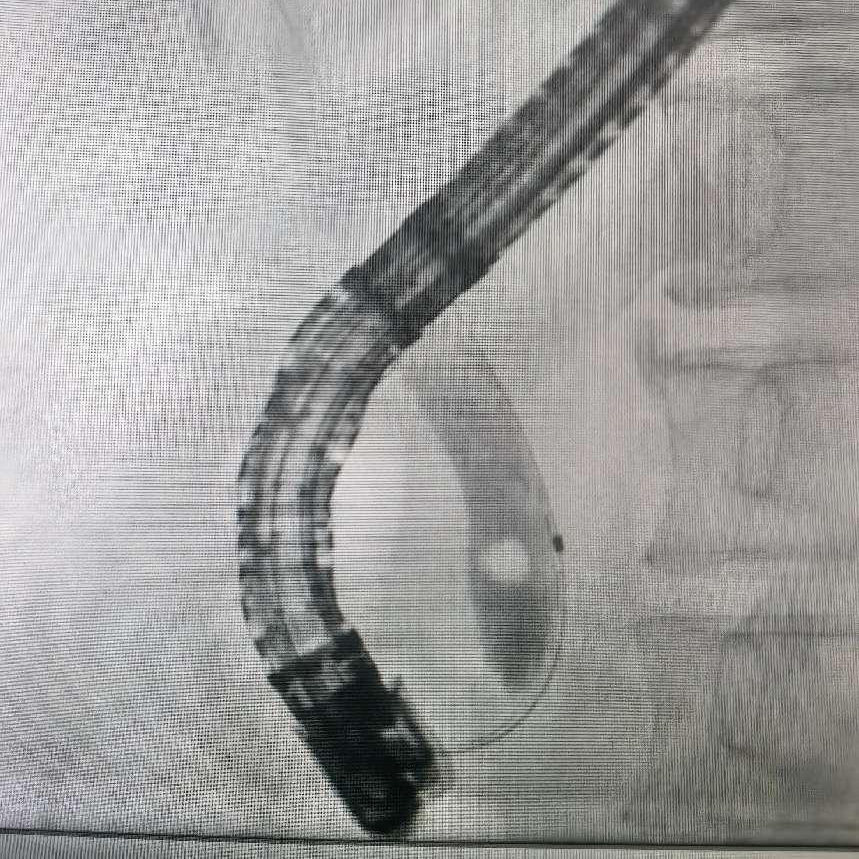

ERCP术中造影见胆总管下段微小结石

ERCP术中取出黄色结石